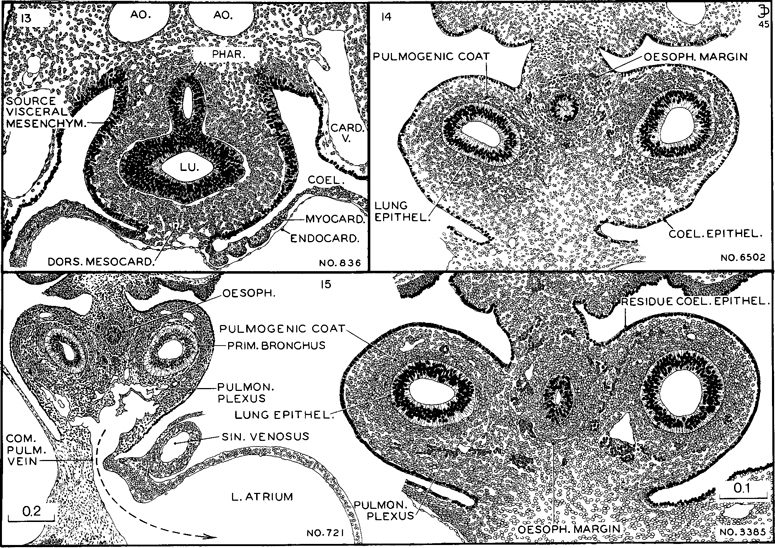

Fig. 15-6. The degree of differentiation of the mesenchymal tissues of the pulmonary and esophageal regions characteristic of stages 13–15. In the least advanced (stage 13) one can still see migrant cells from the proliferating coelomic epithelium. In stage 14 the coelomic epithelium has virtually ceased its proliferative activity and the mesenchyme is arranging itself in zones. Angioblasts are forming a net that outlines the esophagus; a photograph of this section is shown in fig. 14-E. In stage 15 angiogenesis is taking place around the primary bronchi. Large meshes of the pulmonary plexus communicate with the common pulmonary vein, and through it the blood reaches the floor of the left atrium. This is shown in embryo No. 721 of stage 15. The other three sections are drawn to the same scale. All drawings made by James F. Didusch.

To determine the developmental status of the lung where no reconstructions have been made, one resorts to the microscopic appearance of the sections, and important advances can be recognized in that way. The progress in histogenesis is sufficiently rapid to enable one to distinguish between stages 13, 14, and 15, for instance, as is illustrated in figure 15-6. Comparing these three stages, one finds that in the least developed (stage 13) the coelomic epithelium is still actively shedding cells which are moving in toward the alimentary epithelium, forming a layer that envelops the esophagus and lung bud in a common coat of visceral mesenchyme, the primordium of the vascular, muscular, and supporting tissues of these structures. In stage 14 the shower of visceral mesenchyme has ceased and the residual coelomic epithelium is becoming a unicellular layer. Those cells that moved in as visceral mesenchyme begin to exhibit angiogenesis, and as this occurs the investment of the esophagus becomes marked off from the investment of the primary bronchi. The delineation of the esophageal field is aided by the circumstance that angiogenesis first occurs around its margins. It will be seen that a definite advance in differentiation of both pulmonary and esophageal epithelia is present in this group compared with the preceding one. Passing to stage 15, both the esophageal and the bronchial capillary plexuses mark off their respective fields. Forming basket-like networks around the primary bronchi, there is now a conspicuous pulmonary plexus with especially wide meshes between the bronchial tips and the atrial walls. In favorable specimens this can be seen to drain into the left atrium through a main channel, the common pulmonary vein, as shown by an arrow in specimen No. 721, figure 15-6. What is now left of the coelomic epithelium bordering the lung surface will be the source of the visceral pleura.